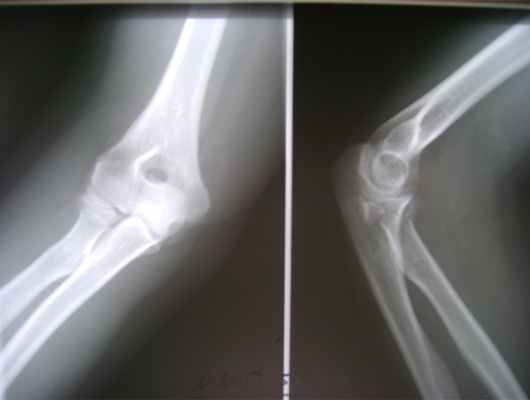

Пациентка И., 39 лет, получила травму локтевого сустава, катаясь на роликах, упав на вытянутую руку. Самостоятельно обратилась в приемное отделение городской больницы 40. При поступлении выполнено рентгенологическое обследование (рис. 1).

Выполнена гипсовая иммобилизация в функциональном положении. Для уточнения диагноза и предоперационного планирования пациентке выполнено КТ-исследование (рис. 2).

Данный перелом можно классифицировать по классификации Mason как тип 3, по классификации АО - 21C3. Учитывая молодой, трудоспособный возраст пациентки, высокие функциональные требования, и сложность перелома - методом лечения выбрано эндопротезирование головки лучевой кости.

Во время операции выявлен многооскольчатый перелом головки лучевой кости (рис. 3, рис. 4).